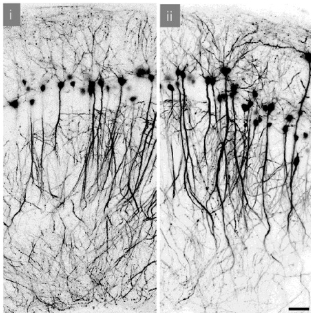

Nimelt on esimest korda ajaloos on õnnestunud osa ajust külmutada ja ellu äratada. Teadusartikkel on kõigile vabalt kättesaadav: https://www.pnas.org/doi/10.1073/pnas.2516848123 (sealt pärineb ka illustratsioon külmutamise-eelsetest ja -järgsetest neuronitest).

Hiire hipokampuse 350 mikromeetri paksusi lõikusid töödeldi jääkristallide teket vältivas lahuses, jahutati vedela lämmastiku abil -190 kraadini ja tulemuseks saadud klaasitaolist materjali hoiti -150 kraadi juures 10 minutist 10 päevani. Pärast seda soojendati preparaate ühtlaselt, pesti välja antifriisid ja tuvastati, et pärast seda ainevahetus toimis, mitokondrid töötasid ja neuronid vastasid elektrilisele simuleerimisele peaaegu nagu normaalsed rakud. Vastavalt simuleerimisele tugevnesid sünaptilised ühendused nagu pidid. Ehk siis - neuronite kogum elas ja õppis, kuni kõiki selliseid preparaate ootava loomuliku surmani 10-15 tunni pärast. Mõningase vaevaga õnnestus säilutada ka terve aju ning hiljem sellest tehtud preparaadid ei erinenud lõikudena säilitatutest.